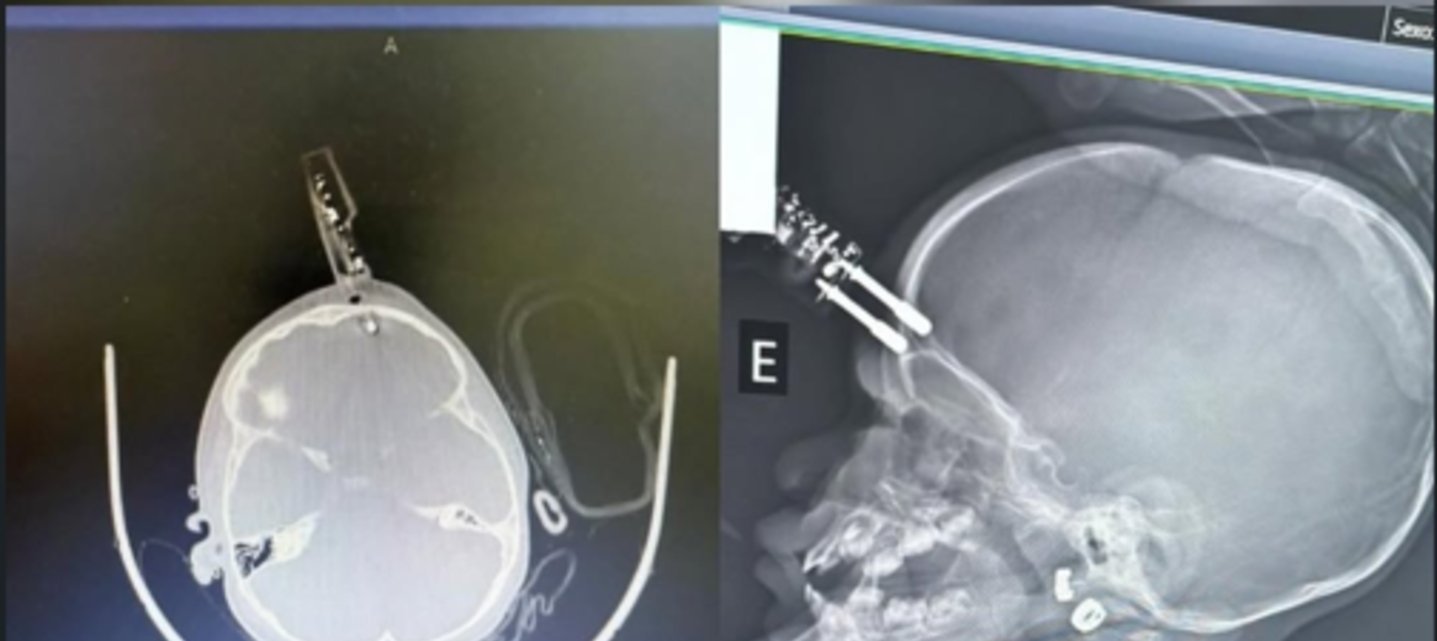

Divinópolis (MG) — Uma menina de 1 ano precisou ser submetida a cirurgia de urgência na terça-feira (13/1) depois de cair da cama e ficar com um carregador de celular cravado na testa.

De acordo com o neurocirurgião Bruno Castro, que realizou o atendimento, a mãe da criança estava no banheiro no momento do acidente. A bebê segurava o carregador quando perdeu o equilíbrio e bateu a cabeça, fazendo com que o objeto penetrasse o crânio.

A vítima foi levada imediatamente ao centro cirúrgico, onde passou por procedimentos de limpeza, retirada do carregador, lavagem do ferimento, sutura e reconstrução da região afetada.